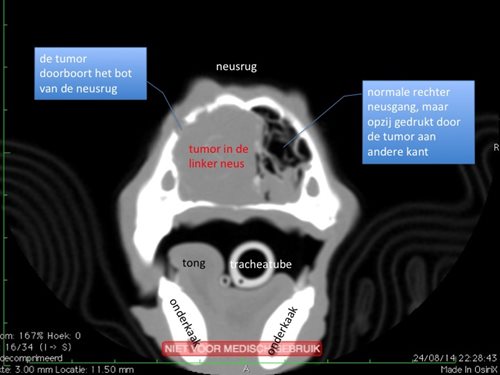

- De doorsnedes laten toe om dingen te zien die anders niet zichtbaar zouden zijn.